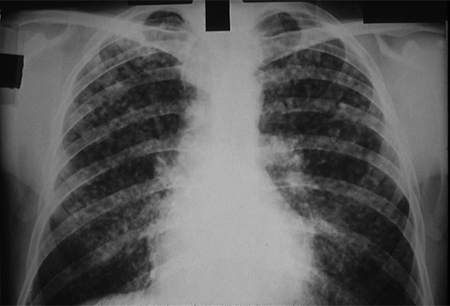

CXR showing changes consistent with simple silicosis or coal workers' pneumoconiosis

From the personal collection of Kenneth D. Rosenman, Michigan State University